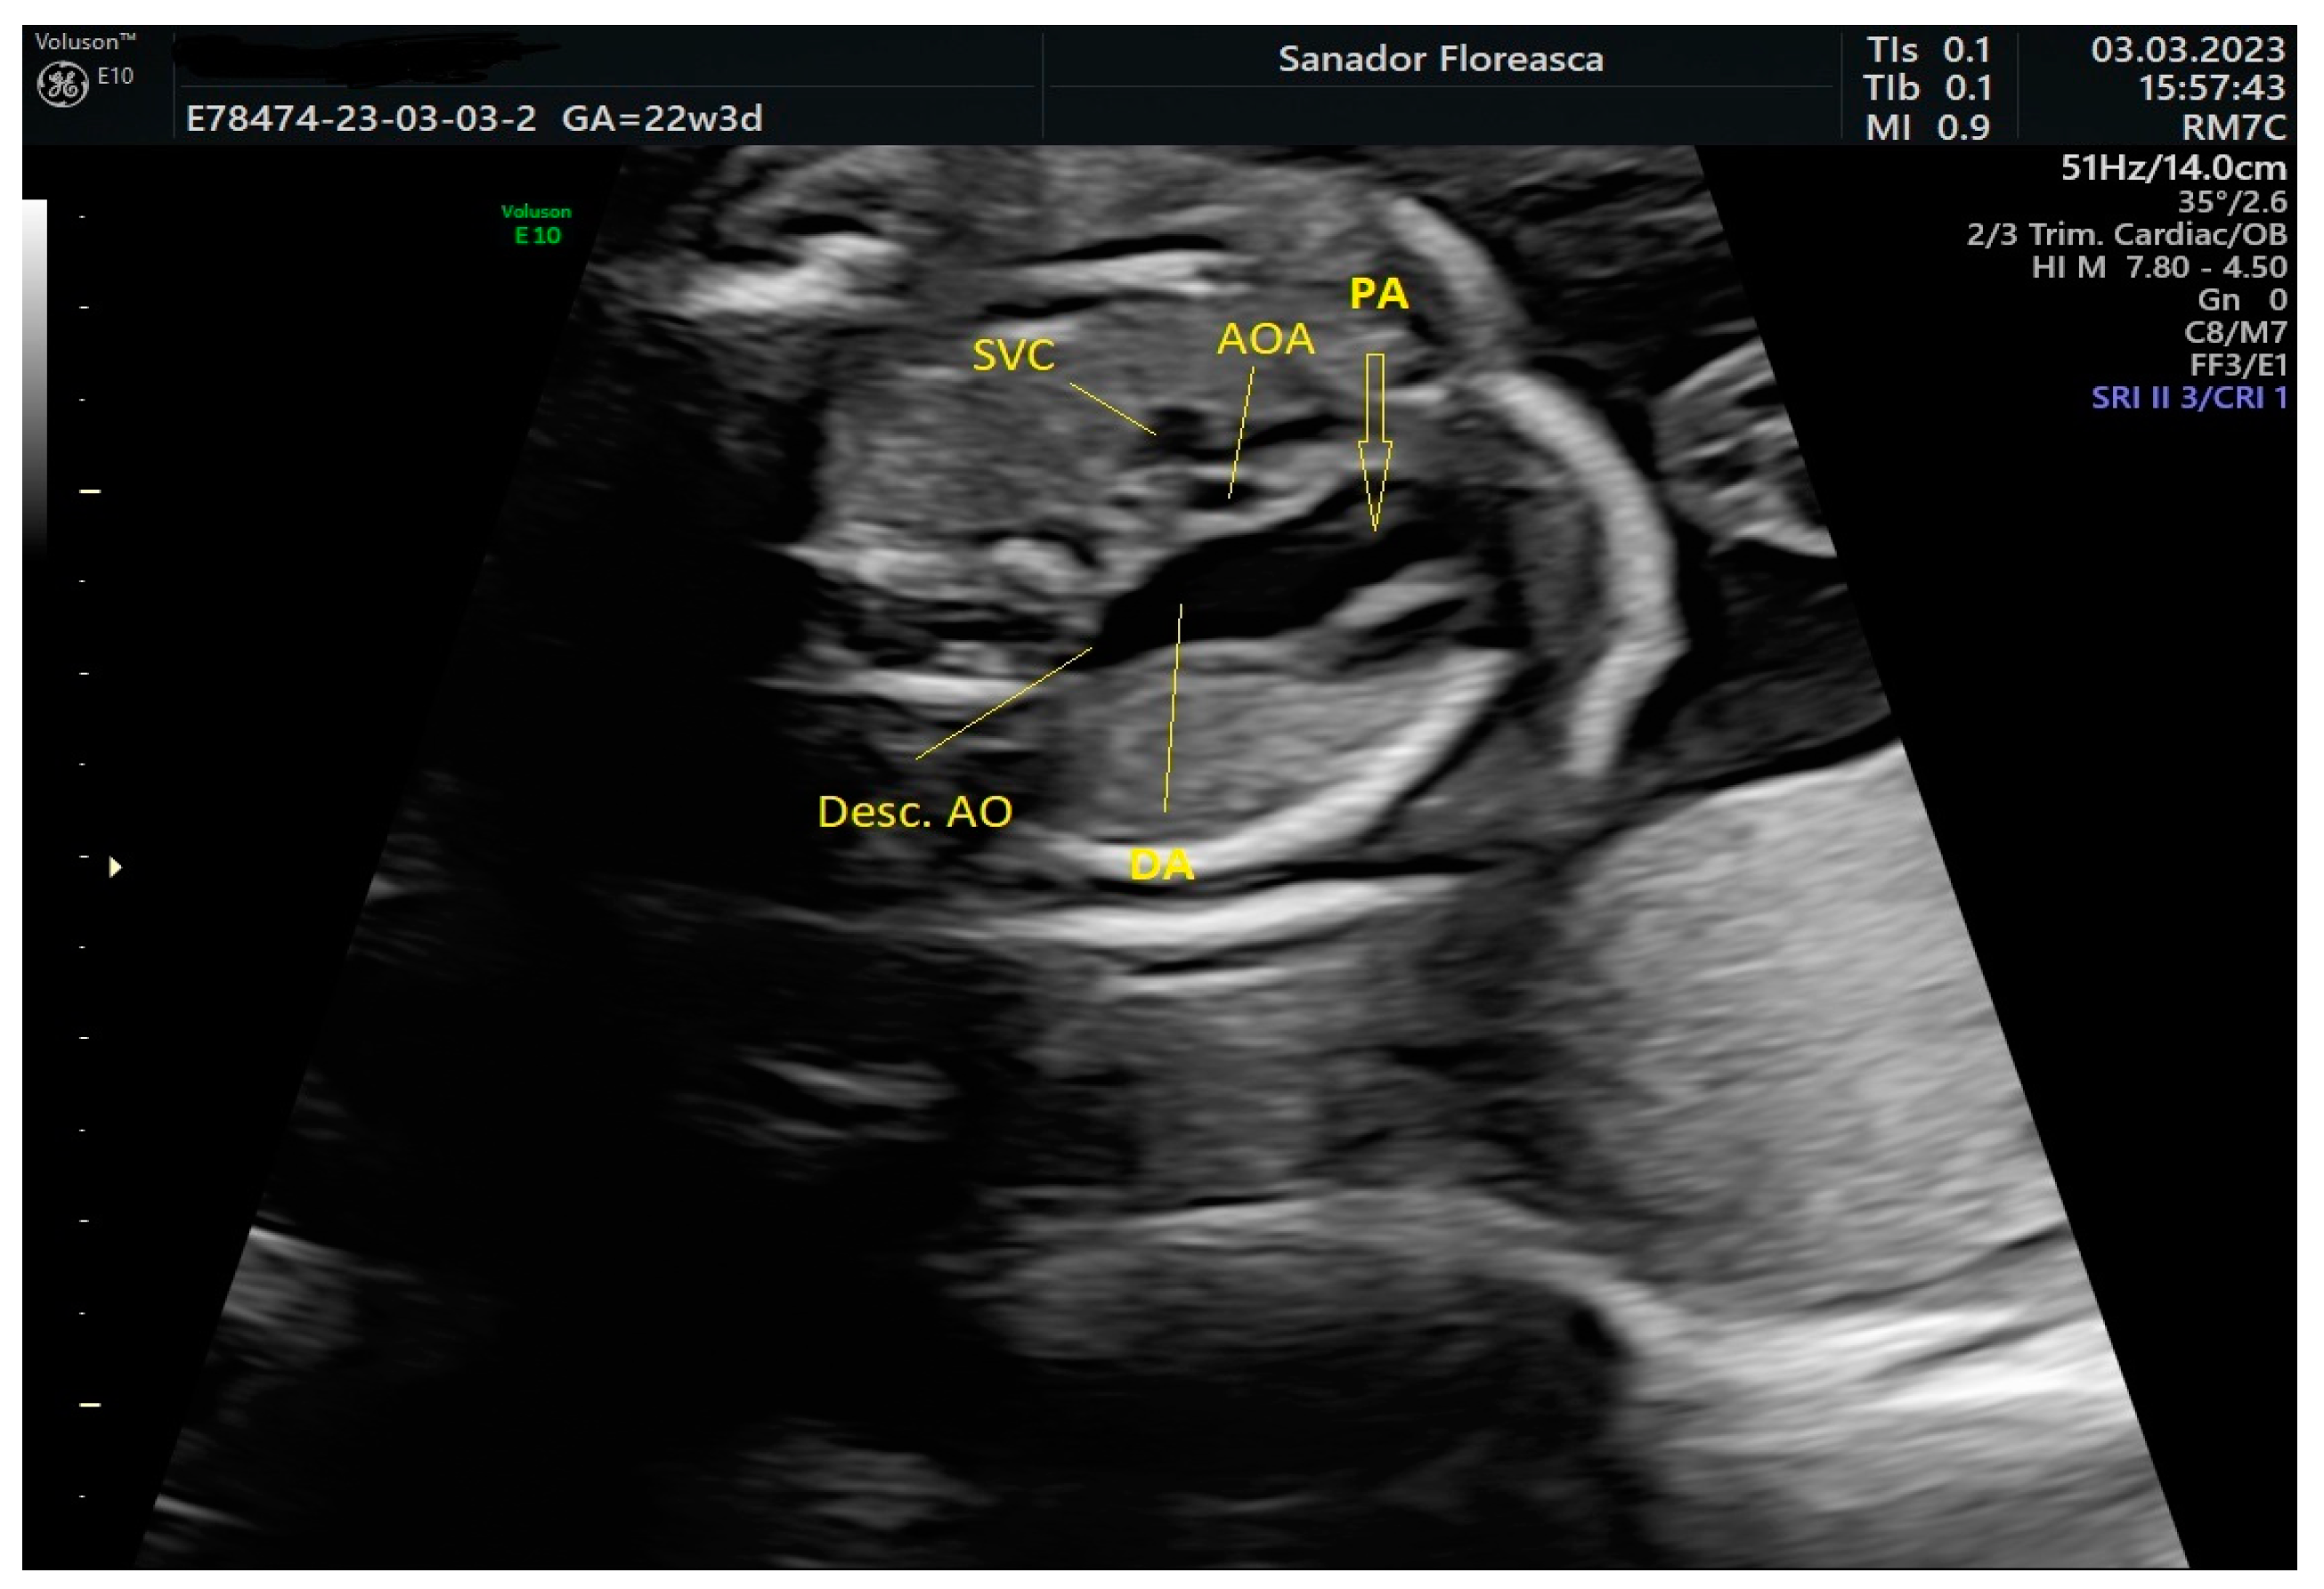

The three-vessel-trachea view revealed one of the main diagnostic features of IAA which is the lack of continuity of the aortic arch; moreover, the trachea appeared in close proximity with the pulmonary artery because of the absence of the medially located aortic arch and the pulmonary trunk was dilated (

Figure 2).

The thymus appeared to be at least hypoplastic and, in consequence, the pulmonary artery was noted to be in close proximity to the sternum anteriorly (

Figure 3). The thymic-to-thoracic ratio was 0.3.